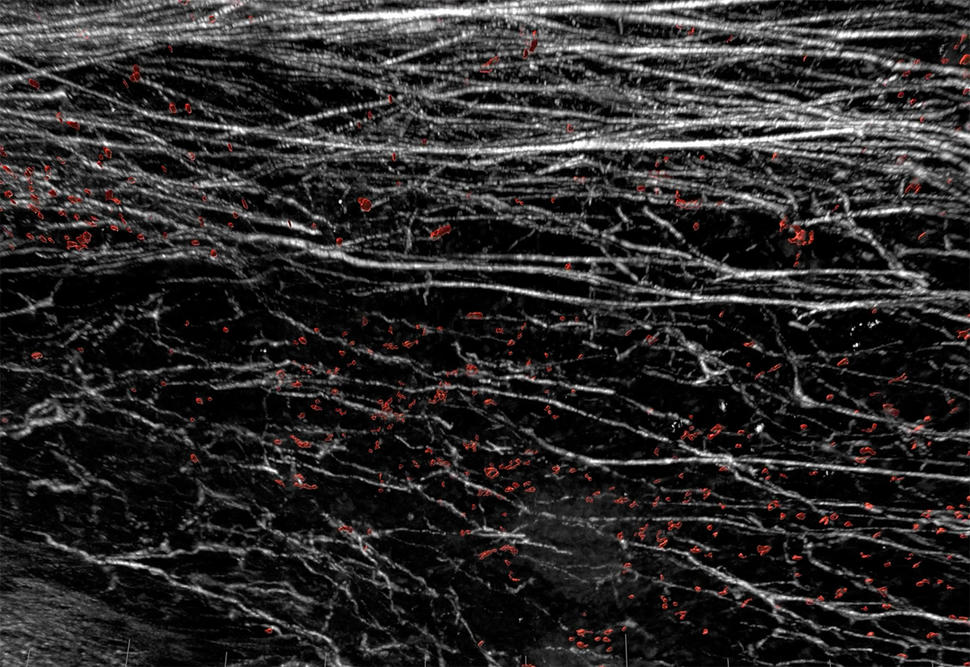

Image of white fiber structures and red cells on black background

Image of a mouse tumor with immune cells (red) being blocked from entering the tumor by a barrier of collagen fibers (grey).

Credit: Used with permission from the George Washington Nanofabrication and Imaging Center

The new findings show that, in mouse models of breast cancer, tumor cells released a segment of the DDR1 protein into the surrounding tumor microenvironment. Here, the molecule appears to orchestrate the alignment of collagen proteins into dense barriers that block immune cells from coming into tumors, the researchers reported in Nature on November 3.

In the experiments, which used mouse models of triple-negative breast cancer, the researchers found evidence that DDR1 promotes the alignment of collagen fibers. The aligned fibers then form a barrier that keeps immune cells from penetrating into tumors.